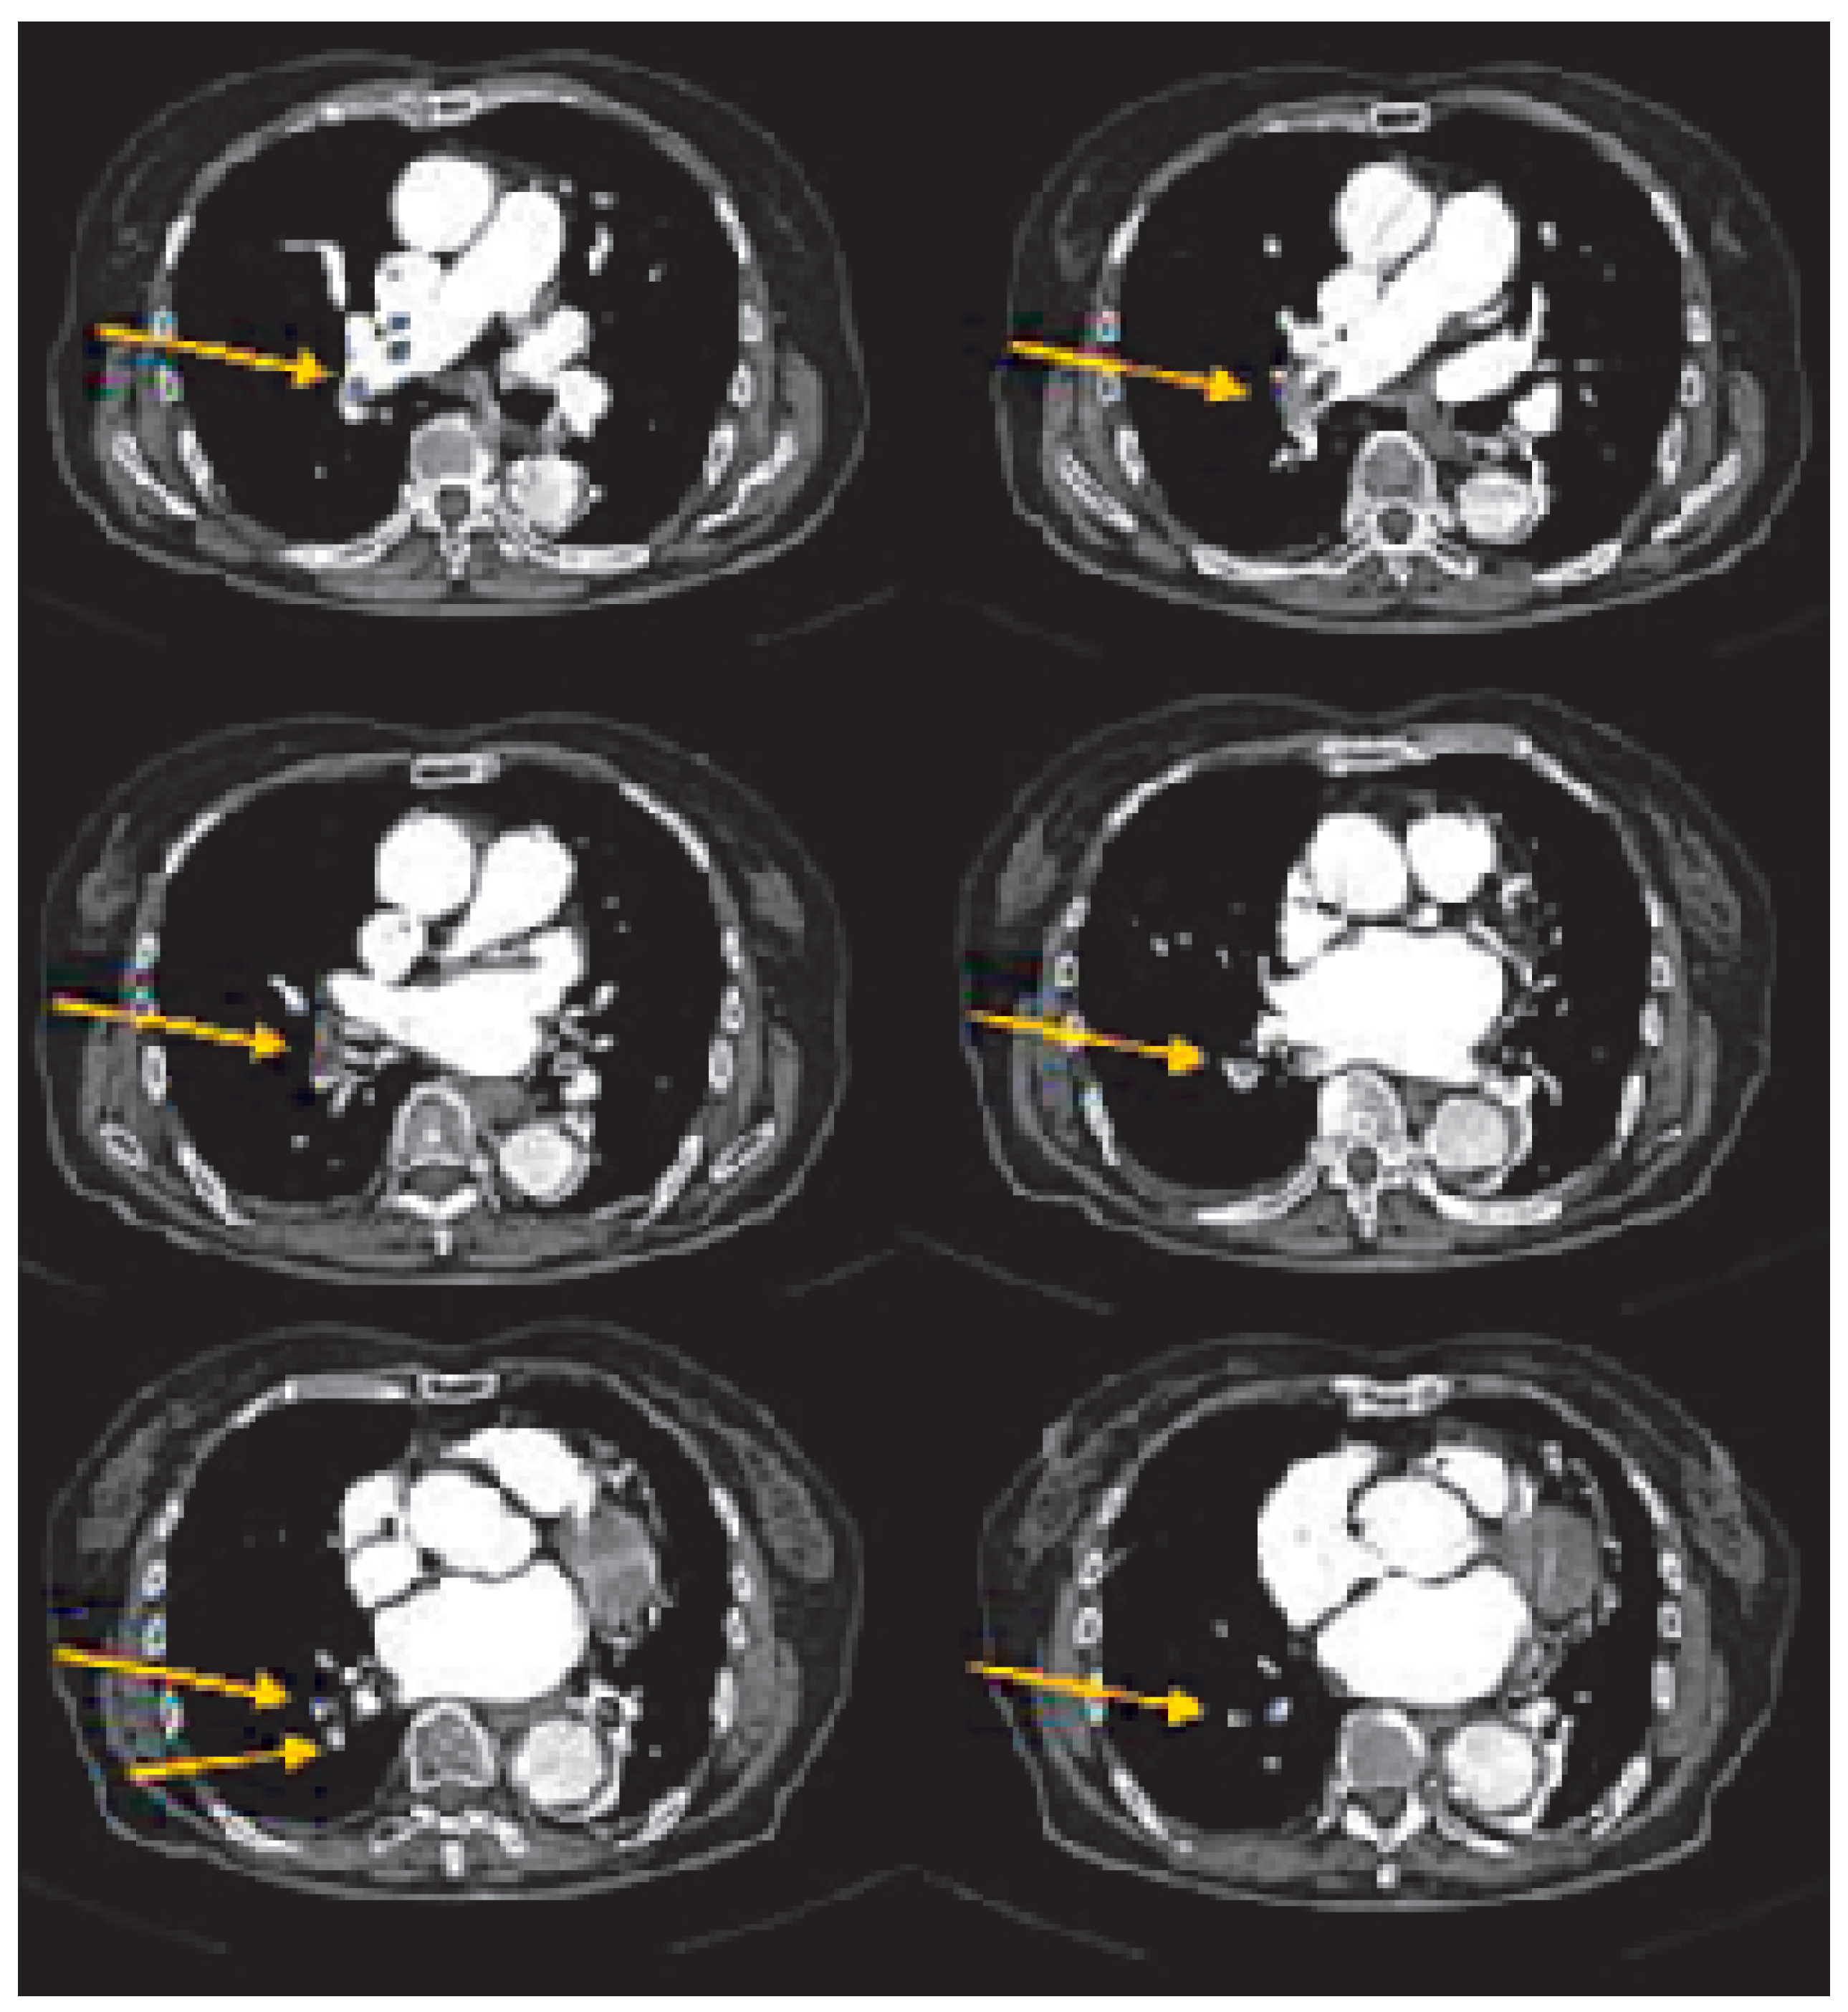

Diagnostic strategy based on spiral computed tomography